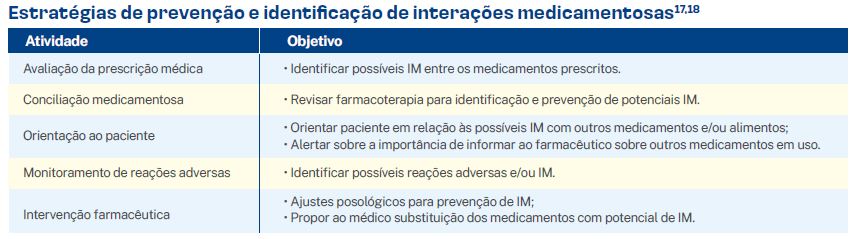

Prevenção e identificação de interações medicamentosas

A atuação conjunta entre o médico e o farmacêutico na prevenção de IM é essencial para garantir a segurança e a eficácia do tratamento. No quadro abaixo, seguem algumas atividades que podem contribuir na prevenção e identificação de IM: